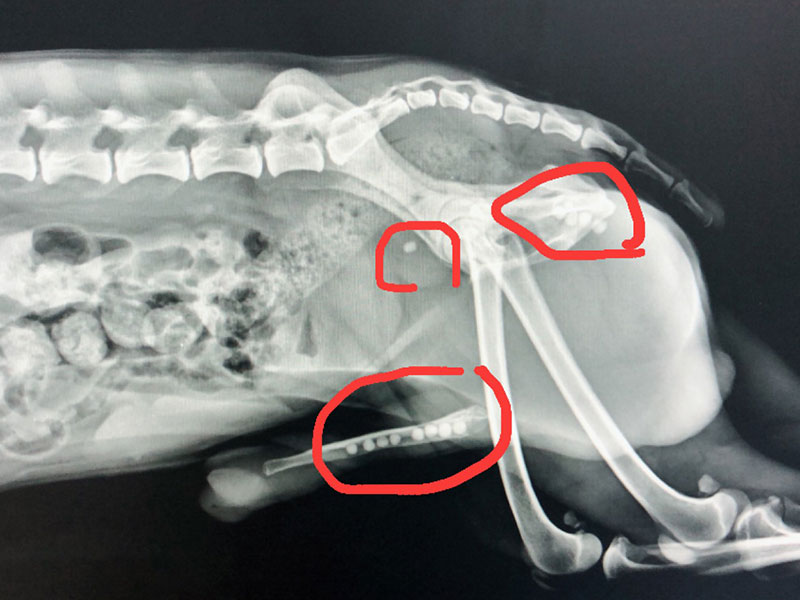

犬 膀胱結石. 犬の尿石症 コーギーの1例 手術で膀胱結石を摘出しました 尿石症とは? 尿石症(尿路結石)とは、尿路である腎臓(腎盂)、尿管、膀胱または尿道のいずれかに結石が形成される病気です。 猫の特発性膀胱炎(FIC) 猫のおしっこに関する病気を総称して猫下部尿路疾患(FLUTD)と呼びます。 その症状として、血尿、頻尿、排尿時に痛がる、ト 排尿障害 〝何度. 膀胱と腎臓を繋ぐ管に出来る尿管結石 3膀胱に出来る膀胱結石 4尿道に石が詰まる尿道結石 犬の結石には4種類あり原因となる野菜・食べ物は異なる. 犬の膀胱・尿道結石の一例 小手指ペットクリニック 16年11月28日 8才のワンちゃんが、昨日から尿が出ずに元気がないとのことで来院されました。 レントゲンを撮ると、膀胱内に7個程度、尿道に3個(ペニス先端から10cmに2個、13cmに1個)の石が.

犬 膀胱結石・尿道結石 チワワ 10歳11ヶ月齢 去勢オス 71kg 頻尿と血尿、排尿障害を主訴に来院 腹部と陰茎の触診検査にて結石症が疑われたため、 レントゲン検査を行い、膀胱結石および尿道結石、腎臓結石と診断した 尿道内にぎっしりとつまった結石は、カテーテルにて膀胱内に押し戻し、膀胱切開にて膀胱結石を摘出した 腎臓結石はに対する外科処置は、腎臓. 犬の膀胱結石 更新日時: ミニチュアダックスフンド、オス (去勢)、11歳 《主訴》血尿、排尿しづらい (少量ずつしか出ない) 《検査》①腹部レントゲン検査 膀胱に結石と思われる不透過性陰影を多数確認 ②腹部超音波検査 膀胱内に結石と思われるシャドーを引く高エコー物を多数確認 ③尿.

一例犬膀胱结石诊疗报告

一例犬膀胱结石的诊断与治疗